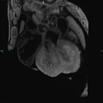

Caption Play Movie2D serial EFIC stack in the coronal view reveals perimembranous VSD, overriding aorta, and right ventricular outflow stenosis (Tetralogy of Fallot type)

Copyright This image is from the Laboratory of Dr. Cecilia Lo, a member of the Cardiovascular Development Consortium (CvDC), Bench to Bassinet (B2B) program of the National Heart Lung and Blood Institute (NHLBI), and is displayed with the permission of the authors. J:175213